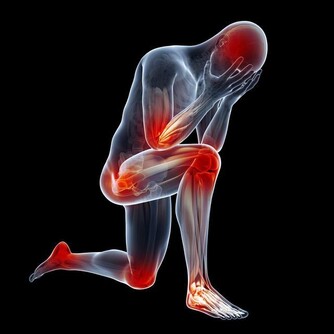

食慾減退和晨起噁心、嘔吐等,是慢性腎衰常見的早期表現。

另外,一些慢性腎衰病人還有一些特殊的臨床表現,如口腔內有氨的氣味,也就是你說的尿味,尿毒症病人更為明顯。

所以,針對你愛人的情況,建議第一,抓緊時間進行正確、規範的治療。